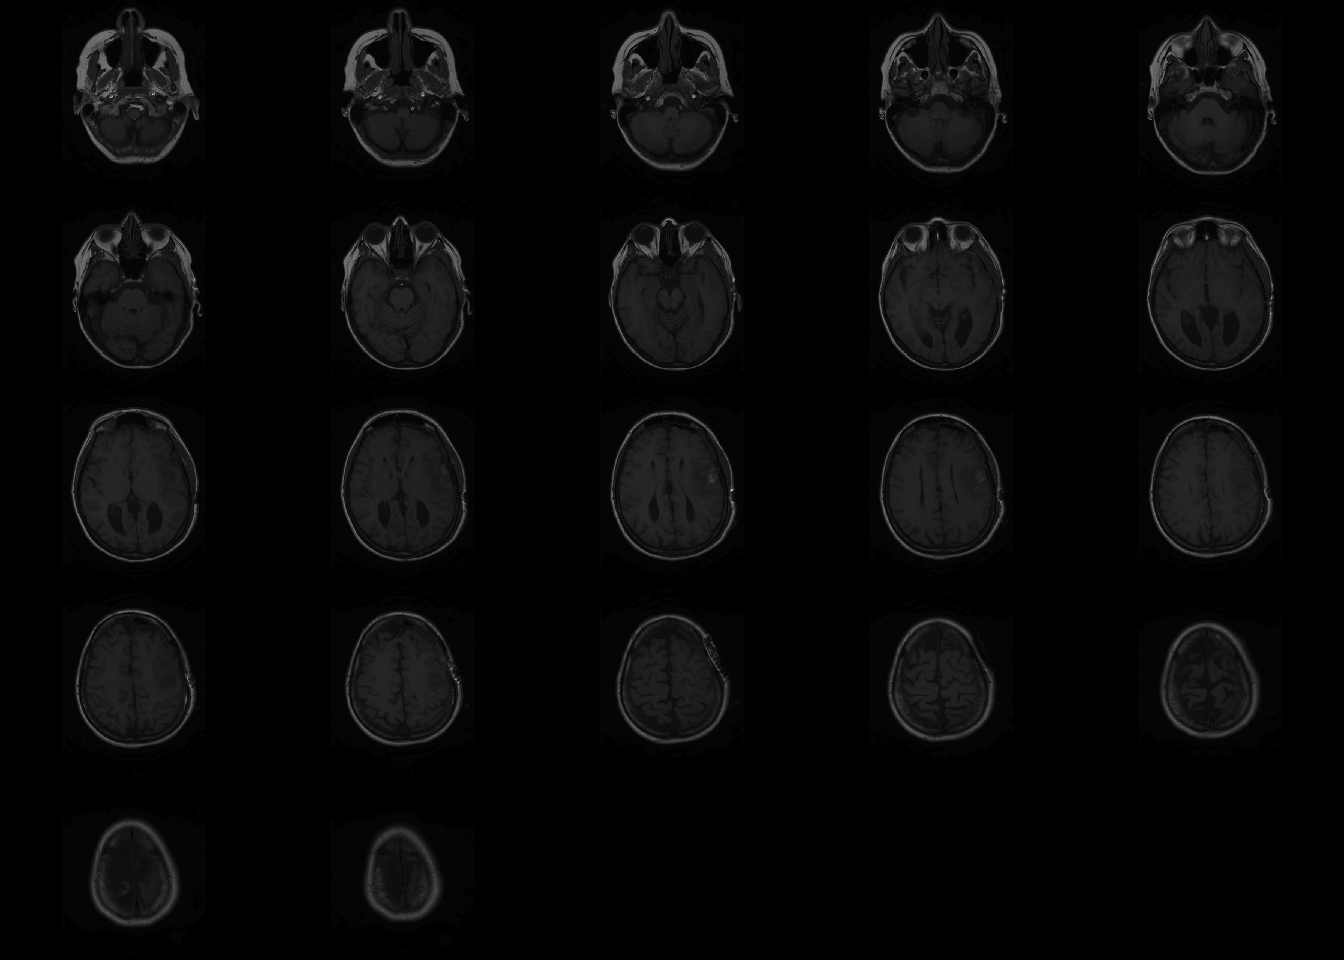

If no arguments are passed for coordinates, oro.nifti::image plots all the slices axially.

The orthographic functions allows to visualize a single point from three dimensions.